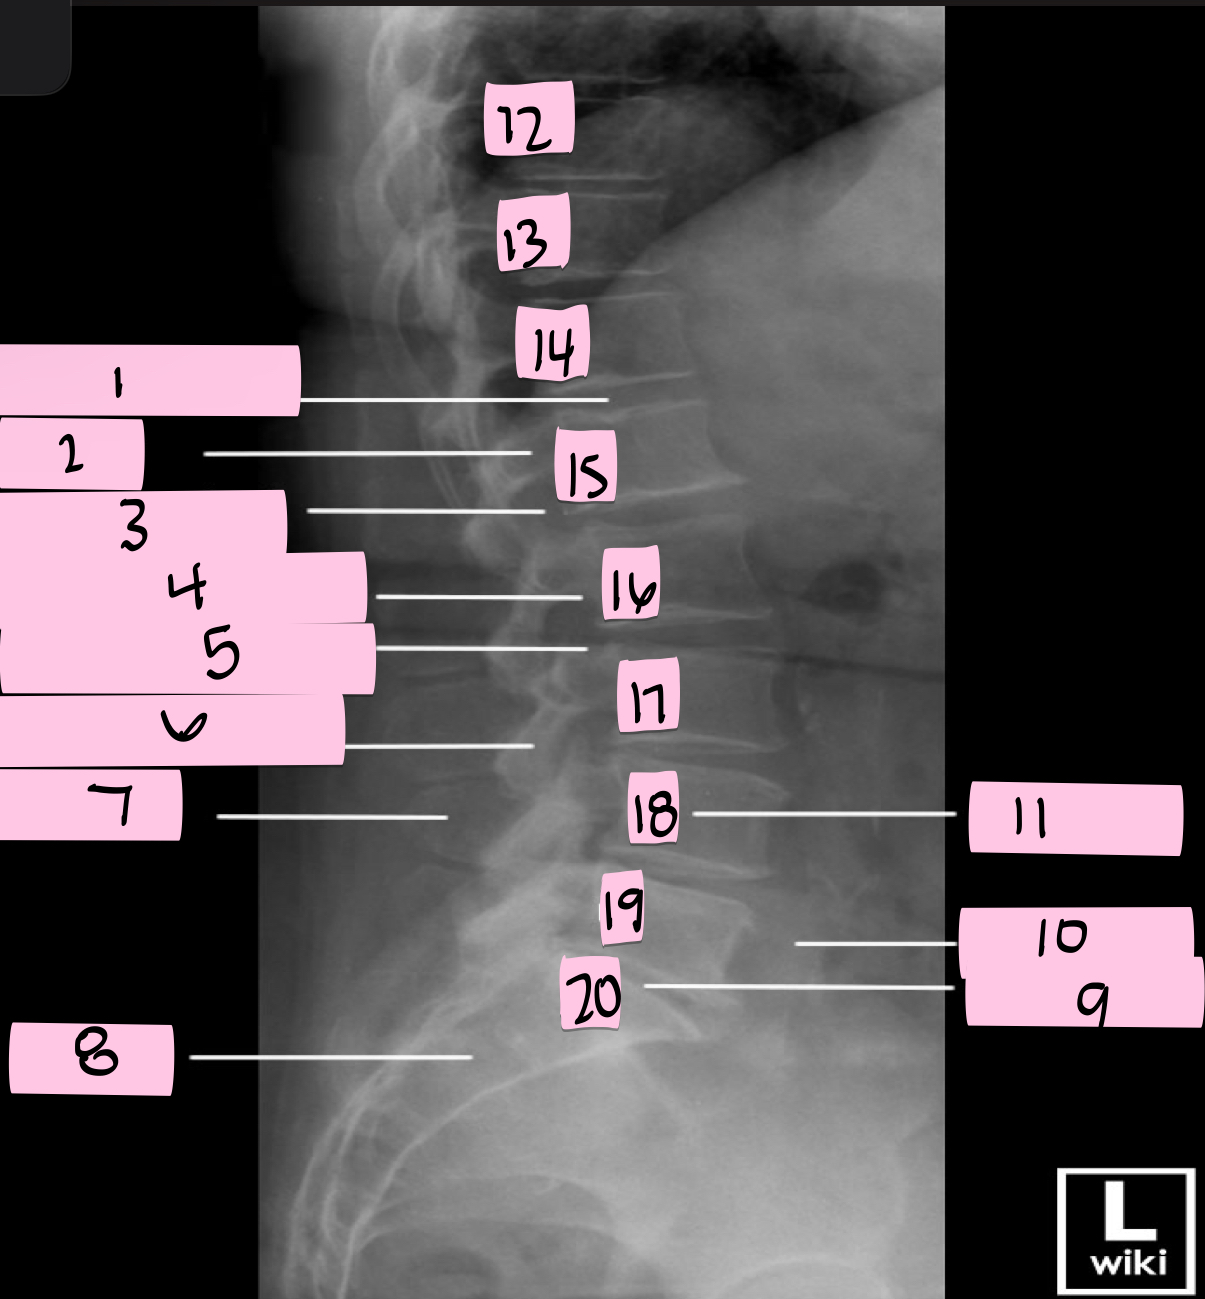

What is 1 pointing to?

Intervertebral disk

What is 2 pointing to?

Pedicle

What is 3 pointing to?

Intervertebral foramen

What is 4 pointing to?

Inferior vertebral notch

What is 5 pointing to?

Superior vertebral notch

What is 6 pointing to?

Inferior articular process

What is 7 pointing to?

Spinous process

What is 8 pointing to?

Sacrum

What is 9 pointing to?

L5 S1 joint

What is 10 pointing to?

Iliac crest

What is 11 pointing to?

Vertebral body (L4)

What is 12 pointing to?

T10

What is 13 pointing to?

T11

What is 14 pointing to?

T12

What is 15 pointing to?

L1

What is 16 pointing to?

L2

What is 17 pointing to?

L3

What is 18 pointing to?

L4

What is 19 pointing to?

L5

What is 20 pointing to?

S1